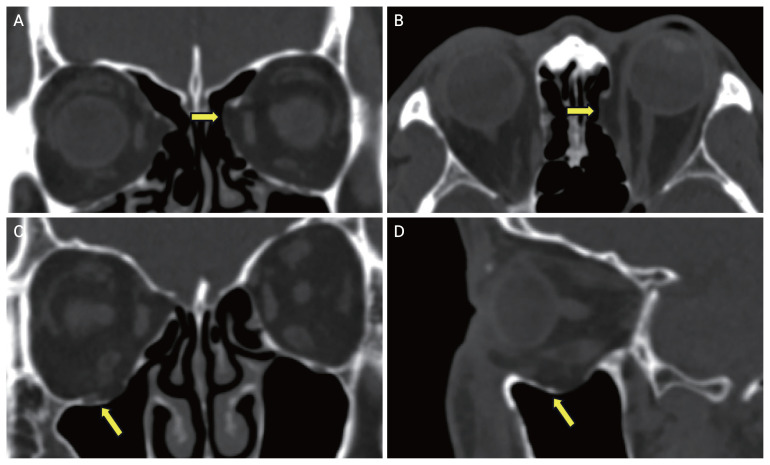

Methods: The medical records of 1,315 ocular trauma patients were reviewed. A total of 927 patients who had orbital or facial computed tomography scans and ophthalmologist evaluations were considered. After applying exclusion criteria, 568 patients with 581 affected eyes were included in the final analysis. The patients were divided into two groups based on the presence of old blowout fractures, identified on computed tomography scan. The clinical characteristics and the frequency of ocular injuries were compared between the two groups. The risk of ocular injury according to the presence of old blowout fracture ware studied using multiple logistic regression after controlling age and sex.

Results: Among the 581 eyes examined, 140 (24.1%) had old blowout fractures. The incidence of intraocular complications was significantly higher in the no orbital fracture group compared to the old blowout fracture group (20.4% vs. 2.1%, p < 0.001). Specifically, the incidence of complications such as gross hyphema (p = 0.001), globe rupture (p = 0.006), and vitreous hemorrhage (p = 0.027) was significantly greater in the group without old blowout fractures than in those with them. Multiple logistic regression showed that the presence of old blowout fractures was significantly associated with reduced risk of ocular injury (p < 0.001).

Conclusions: The patients with old blowout fractures had a lower risk of ocular injuries following subsequent blunt trauma. The findings suggest that old fractures may provide protective effect. These results may have important implications for the clinical management of patients at risk of recurrent orbital trauma.